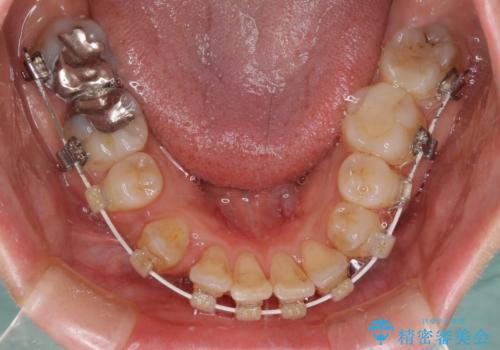

叢生が著しいため、左下以外の第一小臼歯3本を抜去し、目立たないワイヤー装置にて矯正治療を行うこととしました。

- 治療中は違和感や痛みが起こることがあります

- 症状により、抜歯が必要な場合があります

- 治療中は歯磨きがしにくくなるため、虫歯や歯周病になりやすくなります